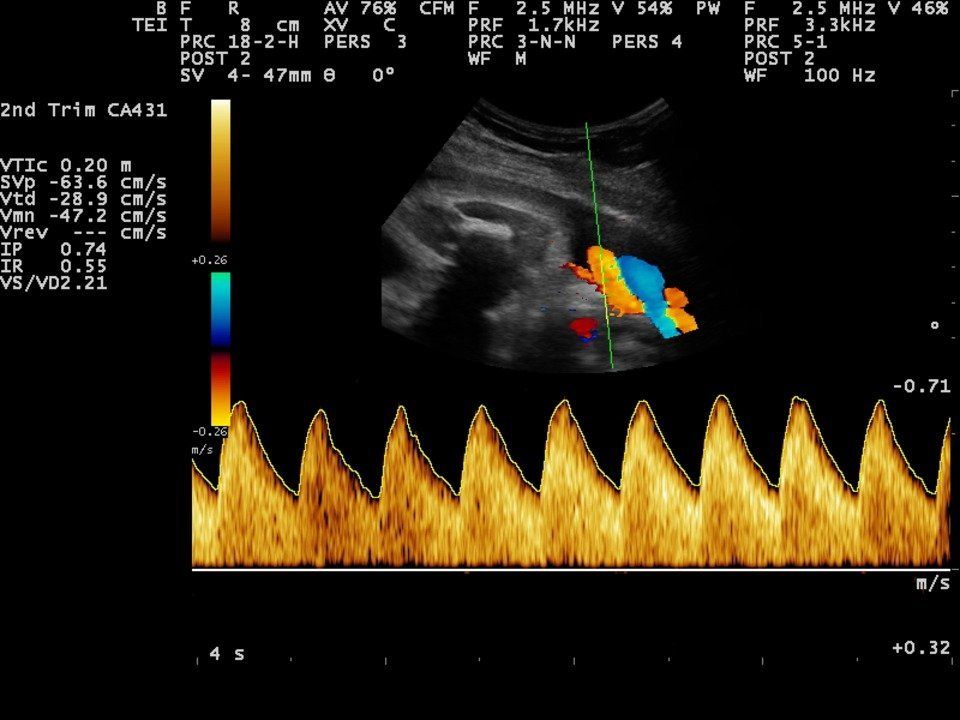

- Umbilical artery Doppler measurement.

- Middle Cerebral Artery Doppler measurement.